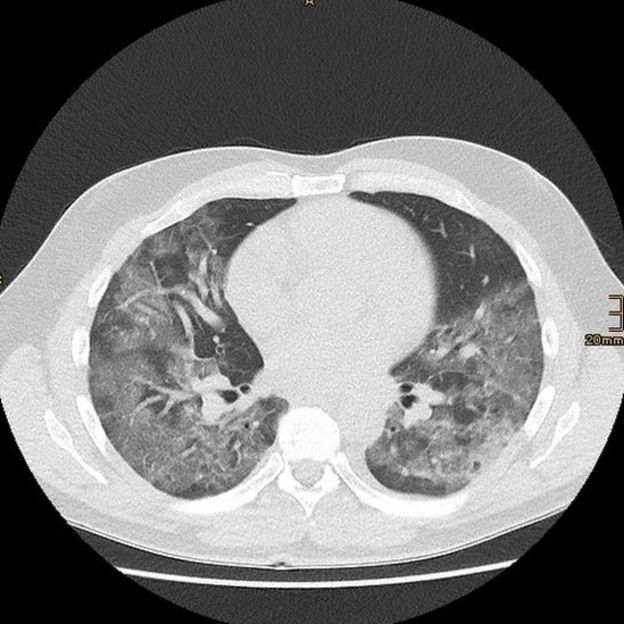

La ciencia detrás de esta temprana lección está emergiendo ahora, con un estudio de Wuhan, China, que describe los cambios patológicos del pulmón en las tomografías de pacientes completamente asintomáticos.

Las tomografías revelan el daño, aunque no haya presencia de síntomas.

Los investigadores encontraron lesiones consistentes con inflamación del tejido pulmonar subyacente (opacidades de vidrio esmerilado y consolidación, para usar la jerga médica), que no son específicas a la infección de SARS-CoV-2 y pueden verse en muchas otras enfermedades pulmonares.

Lo que sigue siendo un misterio es por qué, a pesar de estos cambios, los pacientes no muestran síntomas típicos de neumonía, como falta de aire severa.

El estudio refuerza que la ausencia de síntomas no implica la ausencia de daño.

Las lesiones en una tomografía determinan qué tratamiento se necesita. Todavía hace falta una decisión personalizada basada en el juicio clínico.